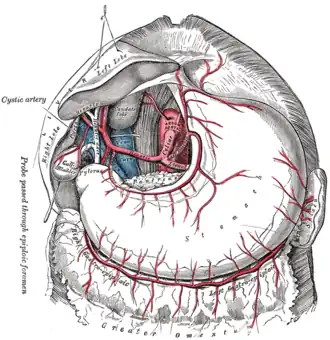

The celiac artery and its branches. (Celiac artery visible at center.) | |

There are three main divisions of the celiac artery, and each in turn has its own named branches:

| left gastric artery[2] | esophageal branch, stomach branch |

| common hepatic artery[2] | proper hepatic artery, right gastric artery, gastroduodenal artery |

| splenic artery[2] | dorsal pancreatic artery, short gastric arteries, left gastro-omental artery, greater pancreatic artery |

The celiac artery may also give rise to the inferior phrenic arteries.

The celiac artery supplies oxygenated blood to the liver, stomach, abdominal esophagus, spleen, and the superior half of both the duodenum and the pancreas.[2] These structures correspond to the embryonic foregut. (Similarly, the superior mesenteric artery and inferior mesenteric artery feed structures arising from the embryonic midgut and hindgut respectively. Note that these three anterior branches of the abdominal aorta are distinct and cannot substitute for one another, although there are limited connections between their terminal branches.)